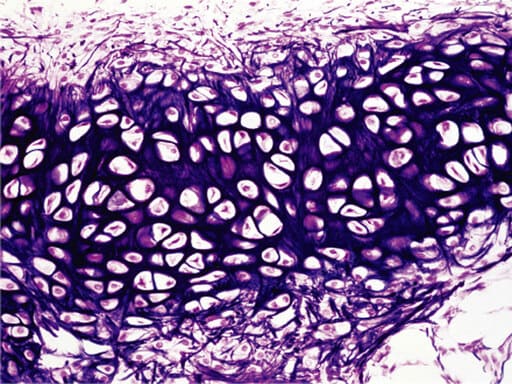

2. Elastic Cartilage

Similar to hyaline cartilage, but contains an abundance of visible elastic fibers that provide greater elasticity and flexibility.

Histology Details:

What is in between the lacunae? A matrix containing visible, dark-staining elastic fibers in addition to collagen and proteoglycans.

How far apart are the lacunae? Moderately spaced, similar to hyaline, but the elastic fibers give it a more flexible appearance.

Function: Maintains the shape of a structure while allowing great flexibility.

Location: External ear (pinna), epiglottis.